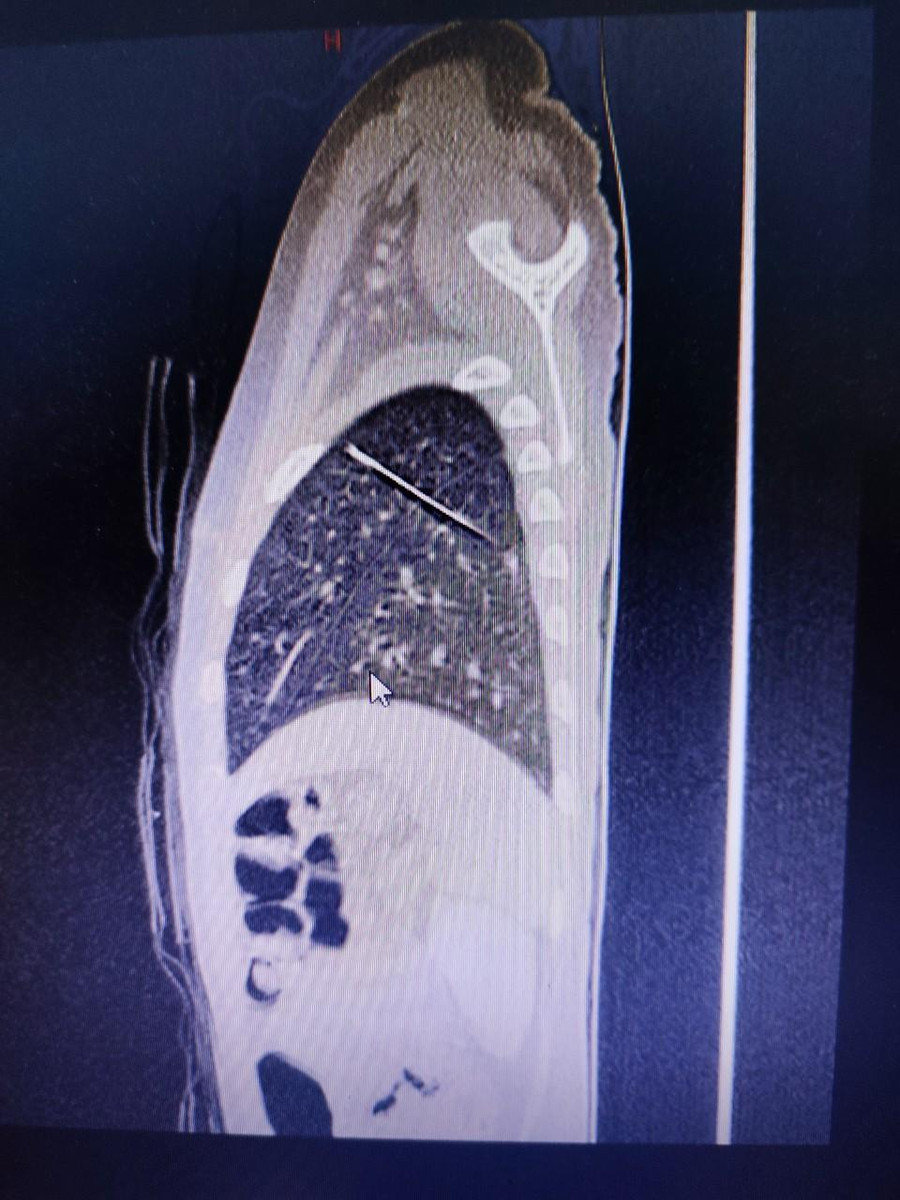

Tại đây, bệnh nhi được thăm khám và tiếp tục được chụp CT scan, ghi nhận dị vật hình dạng kim may áo quần, nằm trong nhu mô phổi trái, xuyên từ thùy dưới lên thùy trên.

| Ảnh chụp cho thấy rõ vị trí chiếc kim may áo quần trong phổi của bé. Ảnh: BV. |